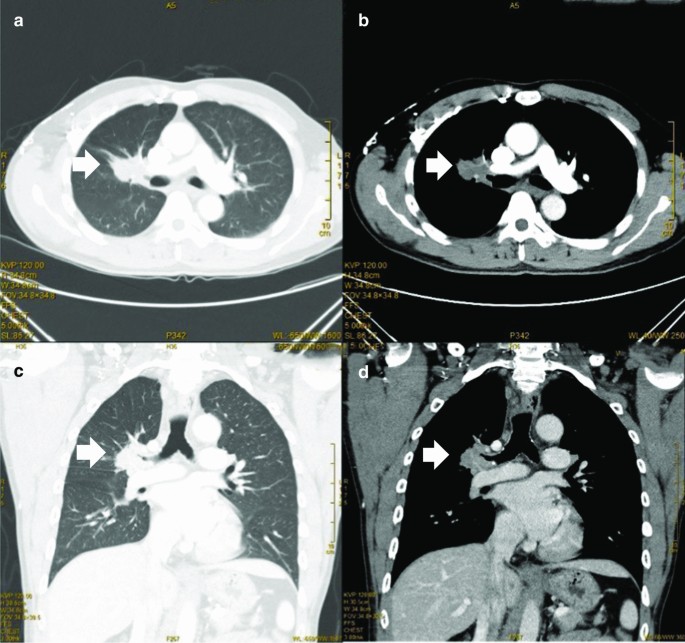

A 54-year-old man diagnosed with locally advanced central squamous cell carcinoma was hospitalized in our hospital. The patient had cough and shortness of breath for 3 months. Chest CT showed central lung cancer in the upper lobe of the right lung, with tumor invading the trunk of the right pulmonary artery, the main bronchus and the upper lobe bronchus (Fig. 1). Squamous cell carcinoma was confirmed by further bronchoscopy. Three courses of neoadjuvant chemotherapy were performed before surgery. The patient refused to continue chemotherapy and asked for active surgical treatment. According to the TNM staging system, the clinical stage of this tumor is cT4N1M0.

Chest CT of right central lung cancer. a. Cross-sectional, lung window showed right central lung cancer. b. Mediastinal window, tumor invaded right main bronchus and right pulmonary artery trunk. c d. Frontal plane, right central lung cancer invade right main bronchus and right pulmonary artery trunk